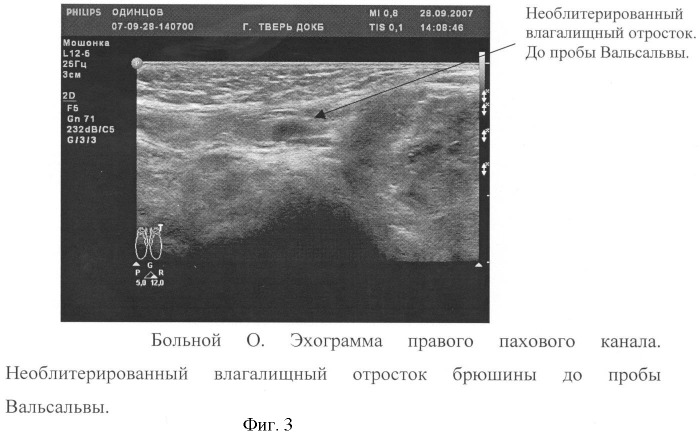

В МЦ «ОЛМЕД» при диагностике паховой грыжи пациента направляют на УЗИ мошонки и половых органов, а также на рентгенологическое исследование органов таза и паховой области. После этого опытные хирурги медицинского центра «ОЛМЕД» определяют характер грыжи и назначают лечение.

Диагностика паховой грыжи:

Основным симптомом паховой грыжи является выявление опухолевидного образования мягкоэластической консистенции в паховой области (или паховых областях). Это образование вправляется в брюшную полость и меняет свои размеры при вертикальном положении больного, при физической нагрузке, кашле или пробе Вальсальвы.

При этом у пациентов с ожирением возможно затруднение при выявлении грыжевого выпячивания. В отдельных случаях это требует проведения дополнительного обследования (УЗИ мягких тканей, МСКТ передней брюшной стенки) с целью подтверждения диагноза либо его исключения.